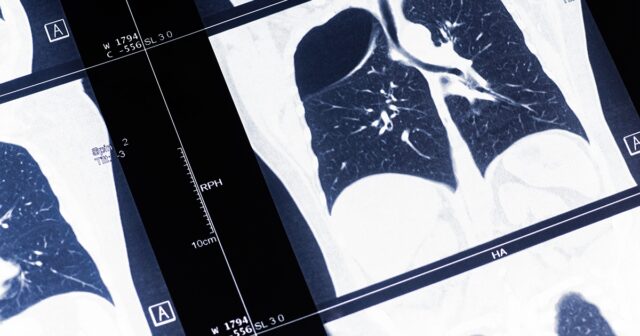

ใครบ้าง ที่ควรมาตรวจคัดกรองมะเร็งปอด ด้วย เครื่องเอกซเรย์คอมพิวเตอร์แบบใช้ปริมาณรังสีต่ำ

เครื่องเอกซเรย์คอมพิวเตอร์แบบใช้ปริมาณรังสีต่ำ ตรวจง่าย ใช้เวลาไม่นาน ผลข้างเคียงน้อย